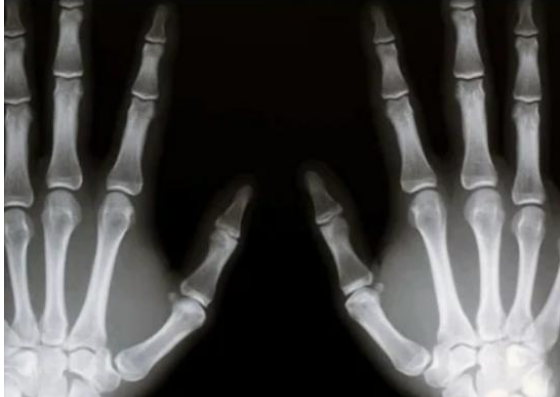

- Kada se tumori formiraju u tkivu kostiju, obično se prvo pojavljuju u dugim kostima ruku i nogu, što je posebno često kod mladih osoba, dok starije osobe mogu biti pogođene tumorima koji nastaju iz tkiva hrskavice. Za identifikaciju bolesti koristi se nekoliko metoda. Rendgenska snimka je obično prvi korak, ona može pokazati promjene u strukturi kostiju. Za točniju procjenu koriste se magnetska rezonancija (MR) ili kompjuterizirana tomografija (CT), ovi uređaji omogućuju točno određivanje veličine i lokacije tumora.